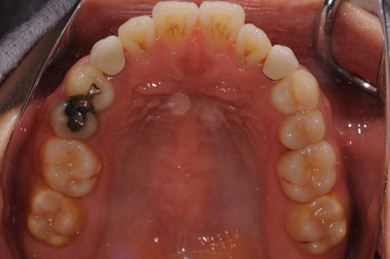

治療前

• 治療前